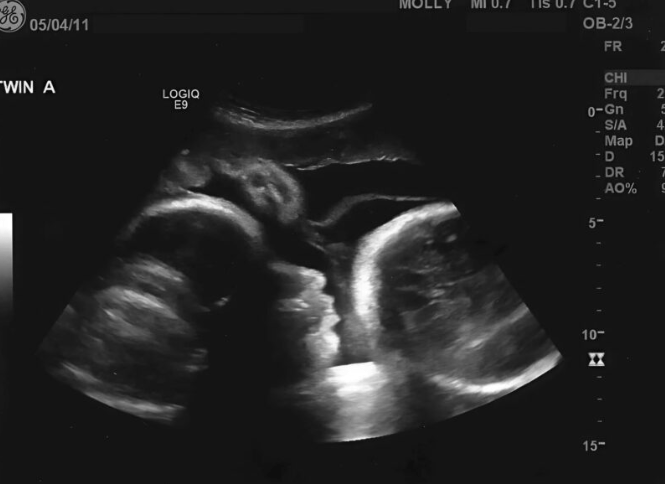

Kada je napokon odlučila da ode kod ginekologa, bilo je to u trenutku kada je bila sigurna da će uskoro roditi. Prošla je devet meseci, prema njenim proračunima, i shvatila da je vreme da sazna kako će se poroditi. Kada je lekar video njen uzrast u medicinskoj kartici, bio je zabrinut, ali nije mogao ni pretpostaviti šta će otkriti. Uradio je nekoliko pregleda i u momentu kada je pogledao slike na ekranu, njegovo lice je postalo bledo. Iako je Larisa bila potpuno sigurna da je trudna, lekar je video nešto što nije imalo nikakve veze sa trudnoćom. Na ekranu nije bilo bebe. Iako su testovi pokazali trudnoću, to nije bila stvarna trudnoća – bila je to posledica ozbiljnog medicinskog problema, koji je uzrokovao da joj stomak raste.